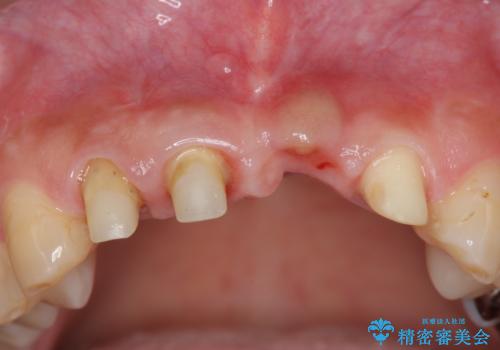

- 前歯の見栄えの悪さの改善を求めて来院されました。

左側の前歯には他院で埋入されたポジションの悪いインプラント補綴により歯冠長の長いクラウンが装着されており、感染による排膿も認められこのまま審美性を改善するのは難しい状態です。